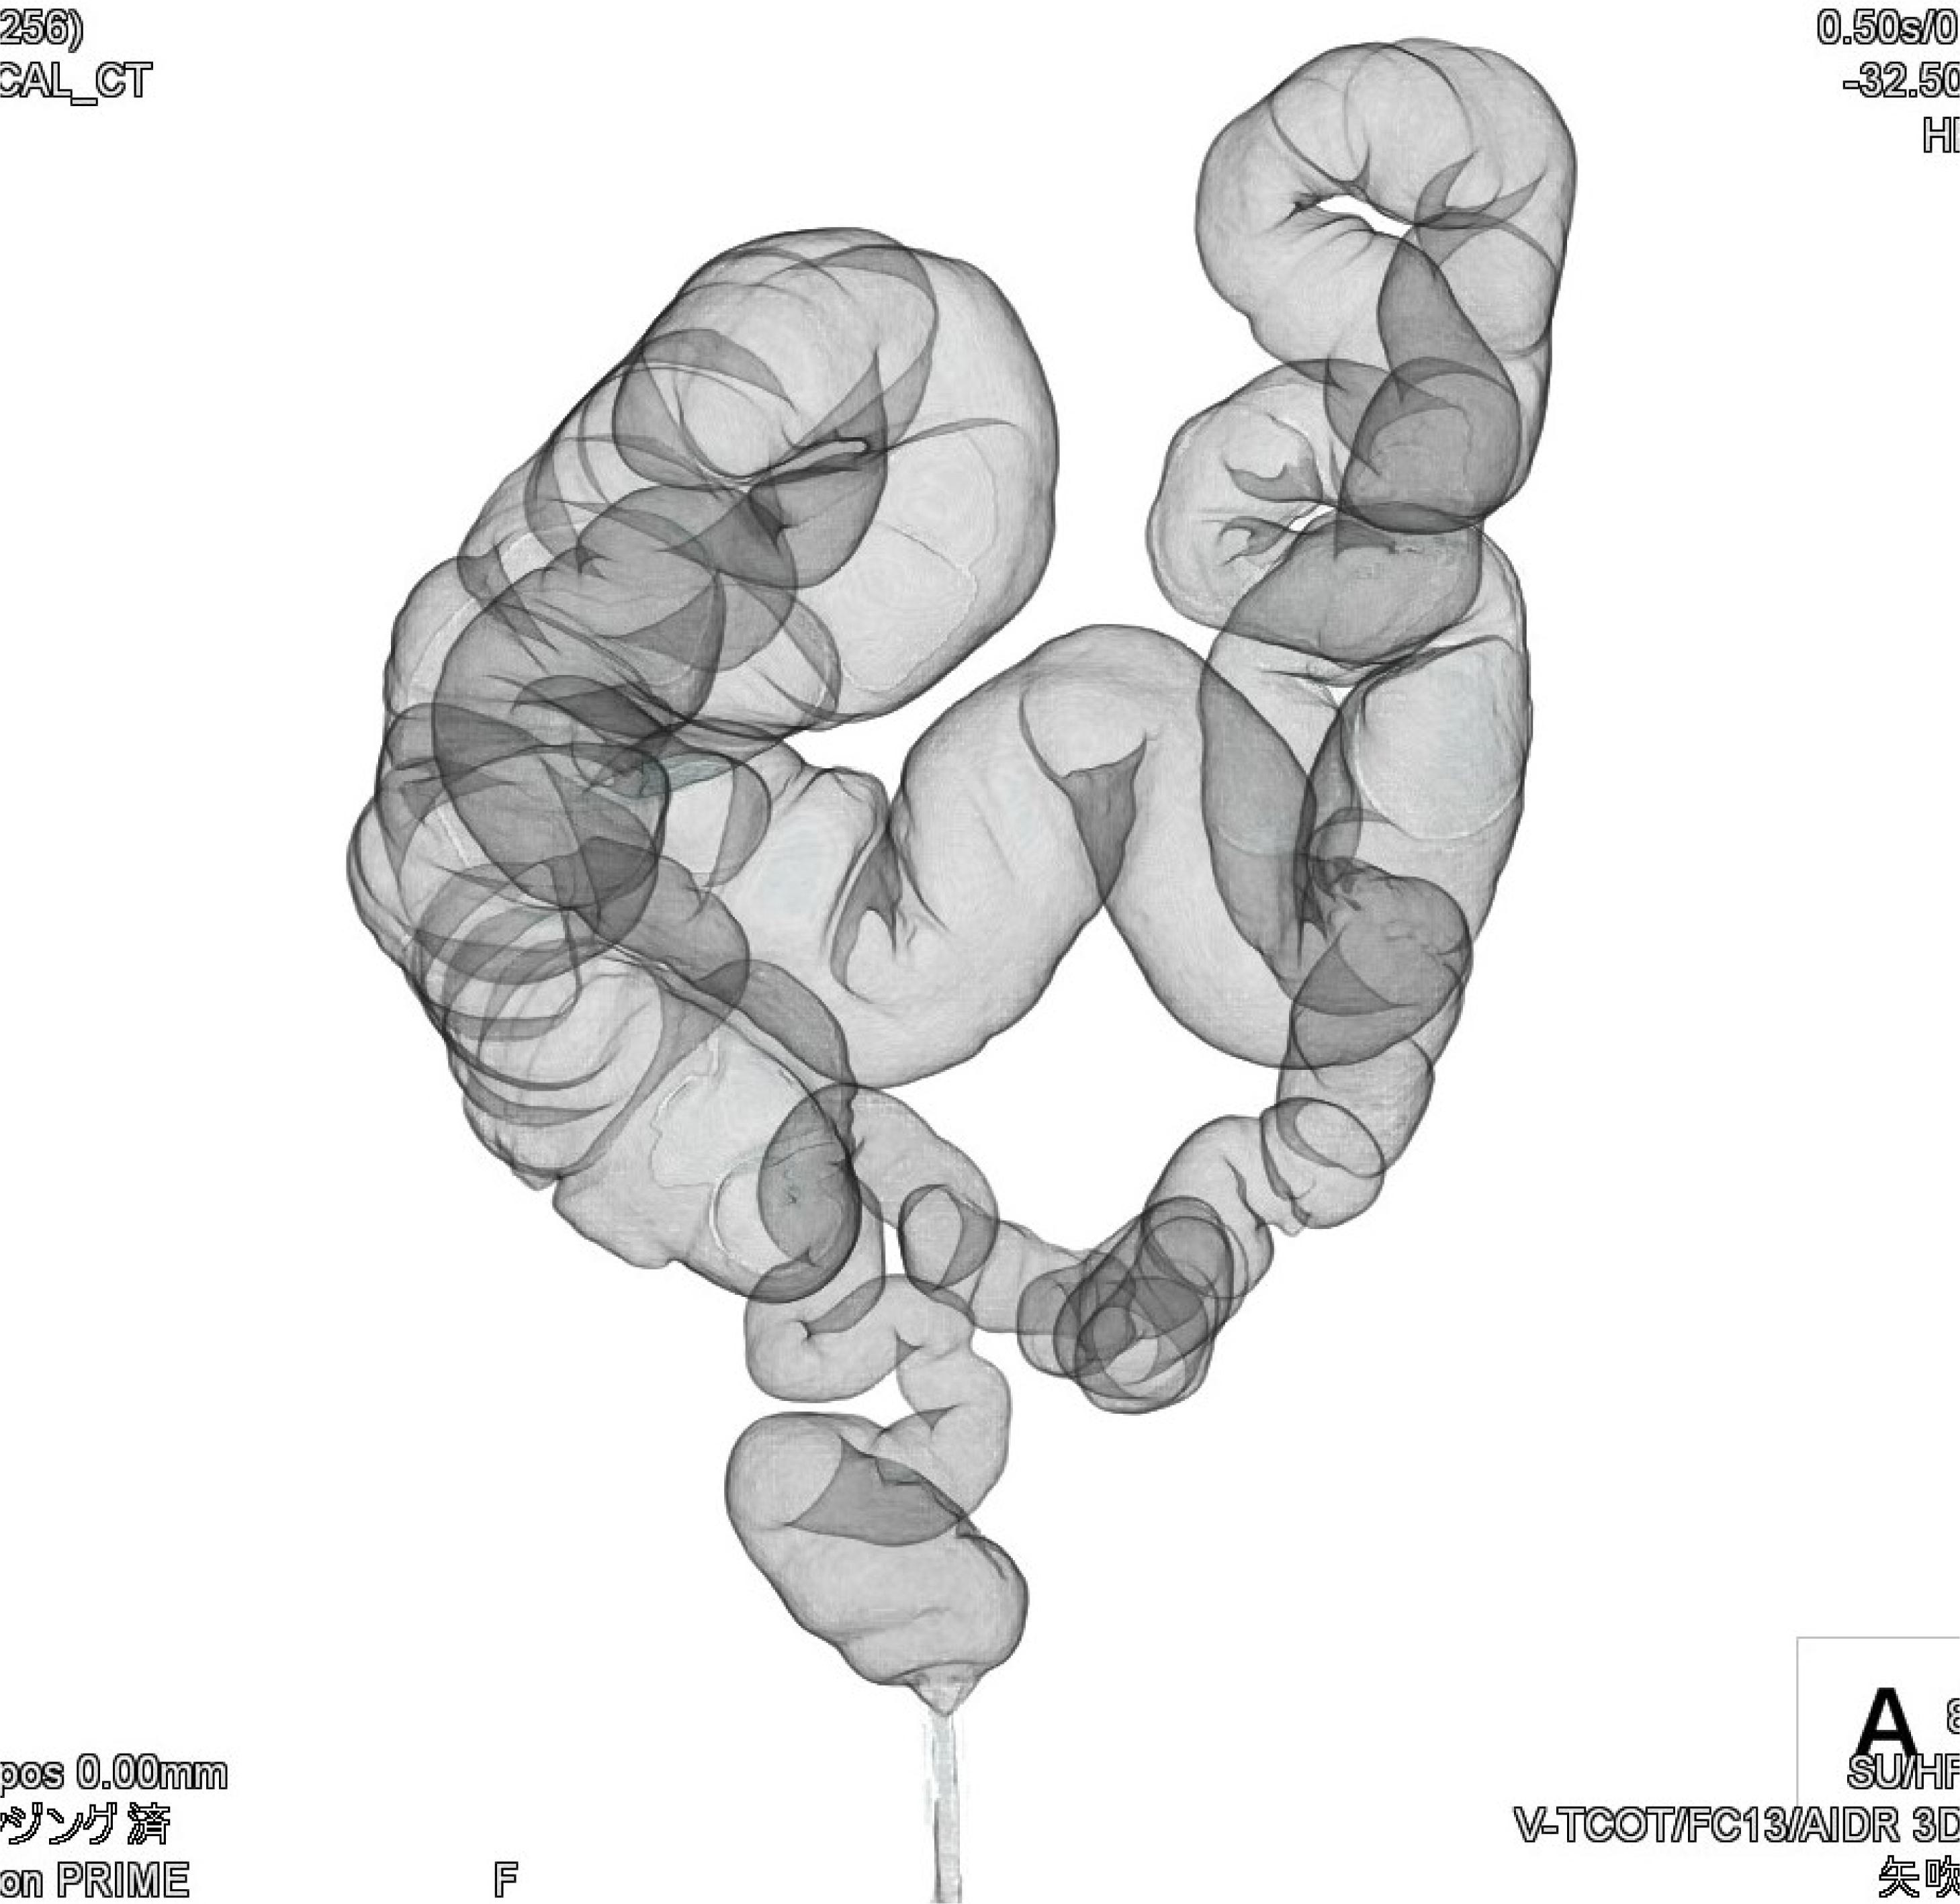

CANON(旧:東芝)社製の80列マルチスライスCTを設置し、胸部・腹部の撮影はもちろん、心臓CTや大腸CT、下肢3DCTといった専門性の高い撮影も行っています。最新のザイオワークステーションを用いて、3D画像作成、心臓解析、大腸の仮想内視鏡検査などを行っています。また、近隣の医療施設からのCT撮影依頼にも対応しており、日々たくさんご利用いただいております。被ばく線量の低減に配慮するとともに、患者さんに合った適切な線量で撮影を行うように心がけています。

心臓CT画像 大腸CT画像